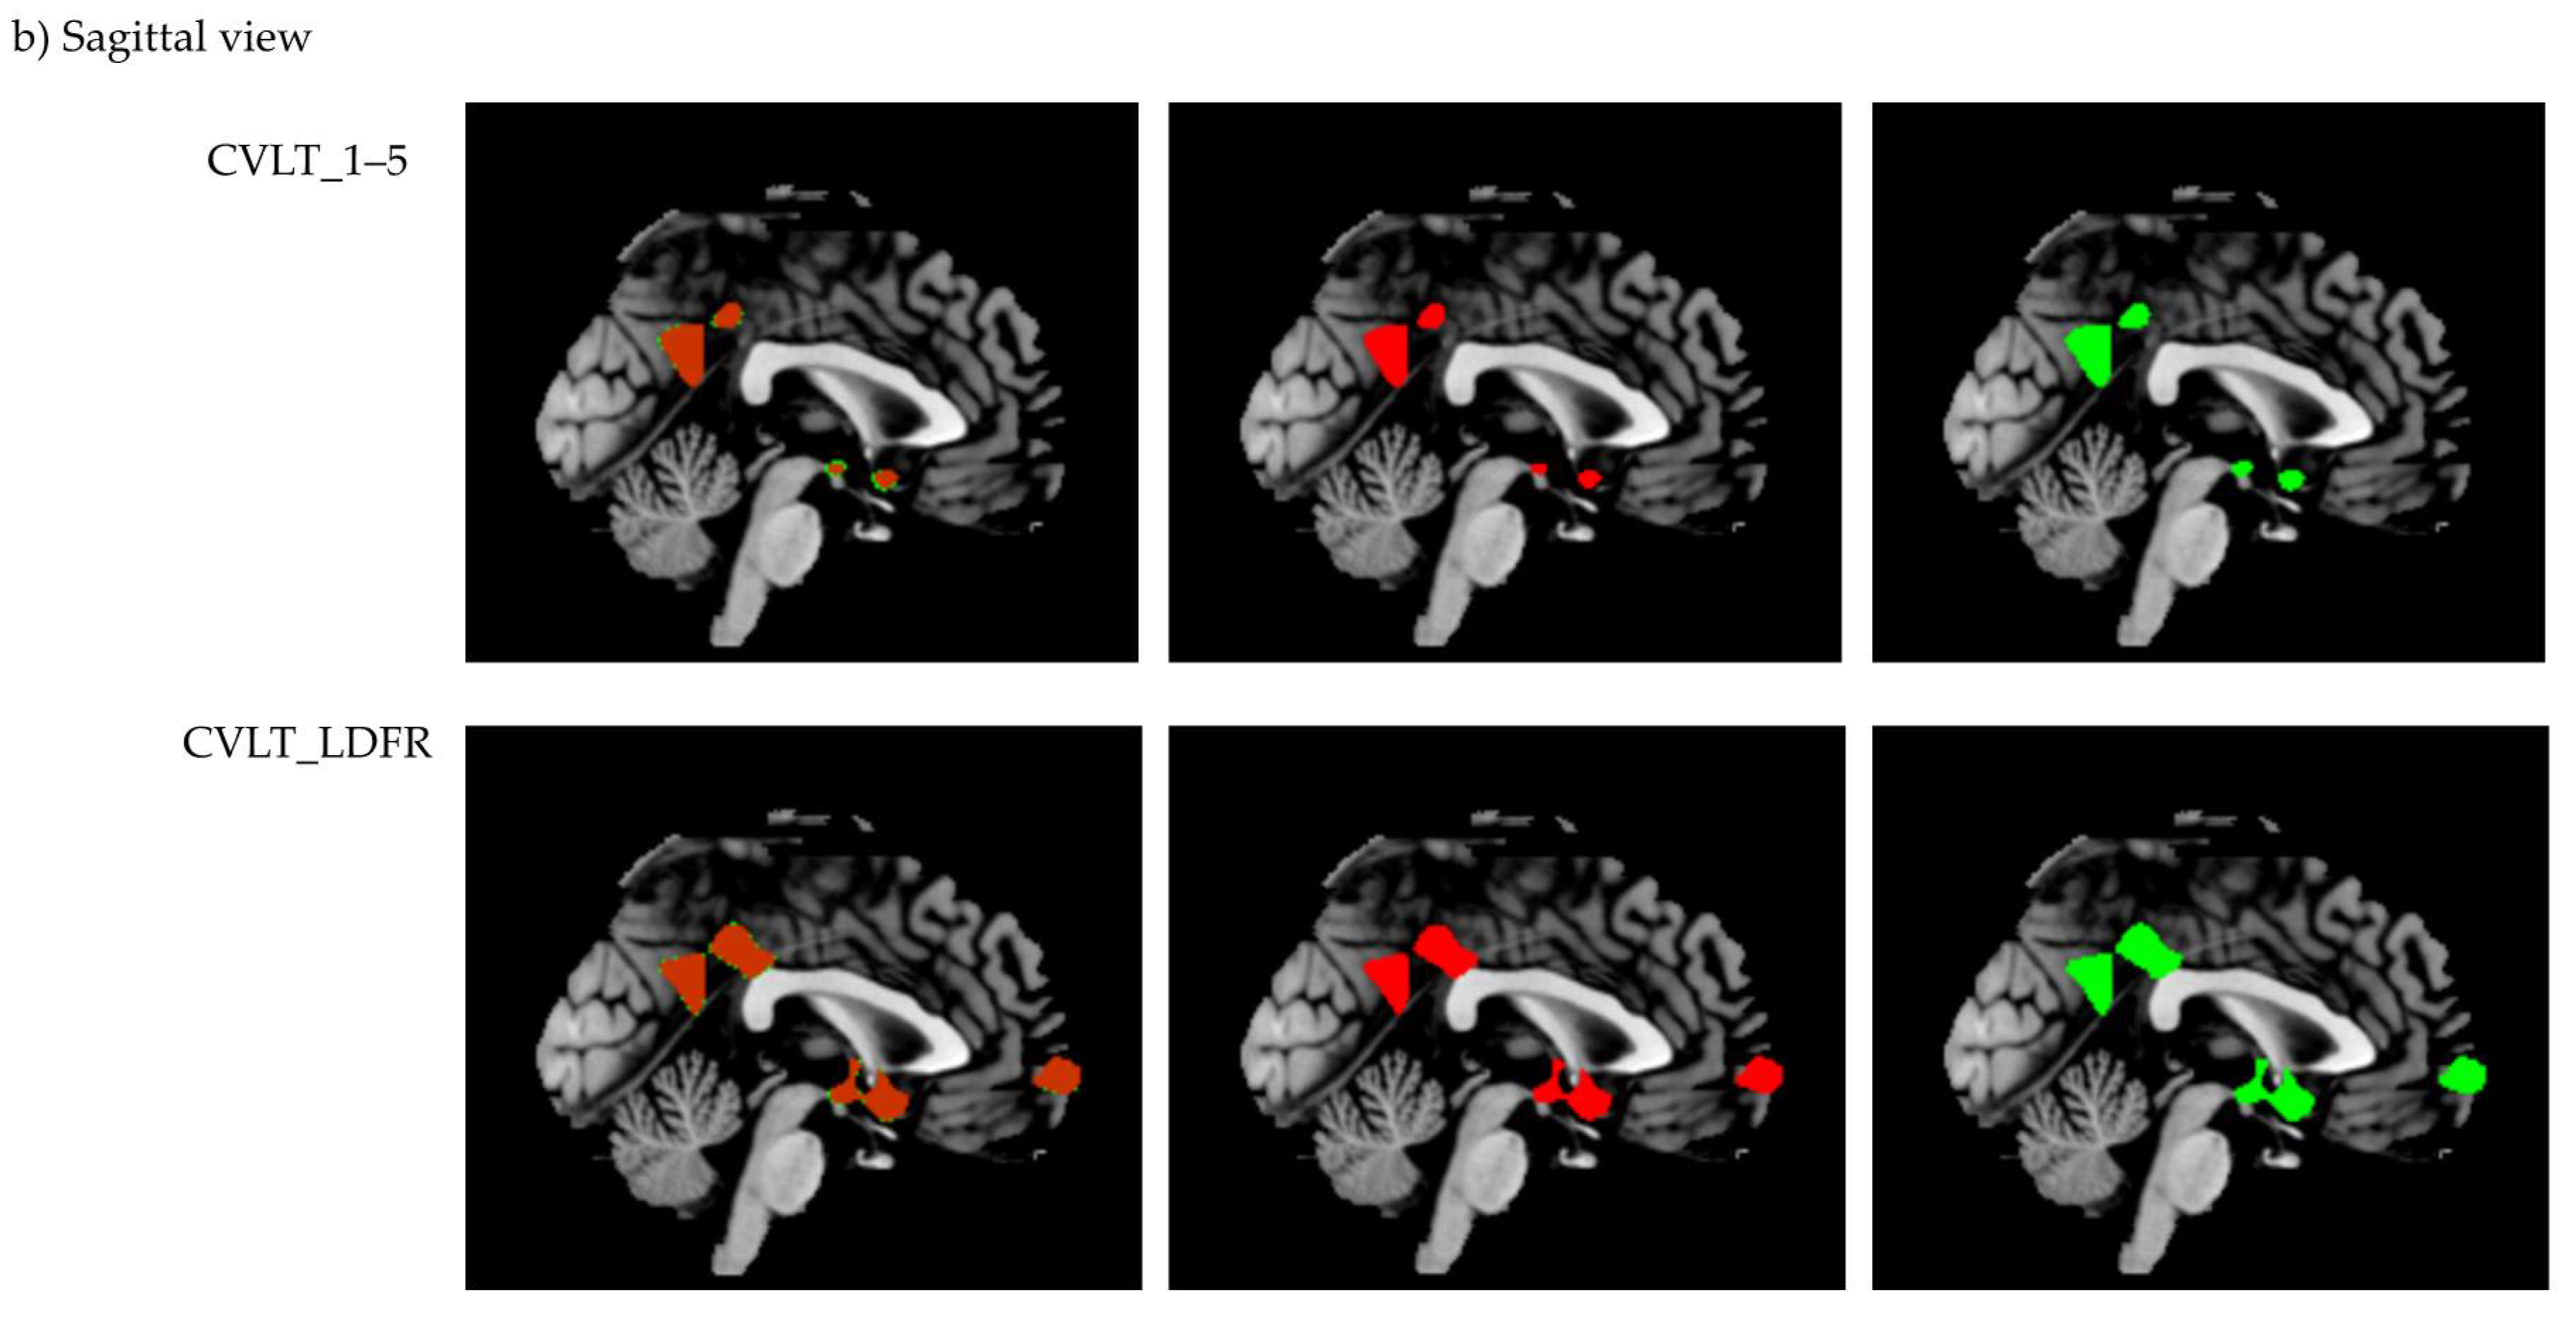

Cluster differences of corrected and uncorrected MRI data are shown in Figure 4.

Figure 4.

Comparison of voxel-based morphometry results for (a) coronal view and (b) sagittal view generated in MRIcron. Displayed is the overlap image, as well as separate images for the corrected (green) and uncorrected (red) data.

In the immediate as well as the delayed free recall condition, VBM analyses revealed significant associations with five clusters that showed identical peak voxels for manually corrected and uncorrected data. In each condition, peak voxel location of a sixth cluster differed only in the x-axis by 1 mm between the corrected and uncorrected data. Furthermore, one cluster showed up only in the corrected data of the immediate free recall condition (middle occipital gyrus, −37, −87, 38). In the delayed free recall condition, one cluster was significant in the corrected (inferior parietal gyrus, −24, −66, 44) and another one in the uncorrected data only (middle occipital gyrus, −30, −89, 22). We think that these differences between the manually corrected and uncorrected data are only marginal. Significant clusters were located in regions expected to be involved in episodic memory, such as the hippocampus, amygdala, and precuneus. Figure 4 shows that results between corrected and uncorrected MRI data differed mainly at the borders of identified clusters and there was no specific pattern regarding the varying cluster sizes of manually corrected versus uncorrected data (see Table 2). For some regions, significant clusters comprise more voxels in the corrected data, while others contain more voxels in the uncorrected data (clusters differ in a range from 105 until 2972 voxels). One reason for this observation is that the accuracy of automated voxel allocation to grey and white matter differs depending on brain region and diagnosis. In normal aging, for example, studies reported preservation of grey matter volume in structures such as the amygdala and hippocampus [,,]. These are precisely the regions showing more voxels in the uncorrected data. Ashburn and Friston [] noted that voxels sometimes contain a mixture of tissues and usually appear as grey matter when located at the interface between white matter and ventricles. As we combined images from the NC and AD groups, signal intensity could have affected the primary assignment of voxels to grey or white matter and thus might have manipulated the manual misclassification correction.